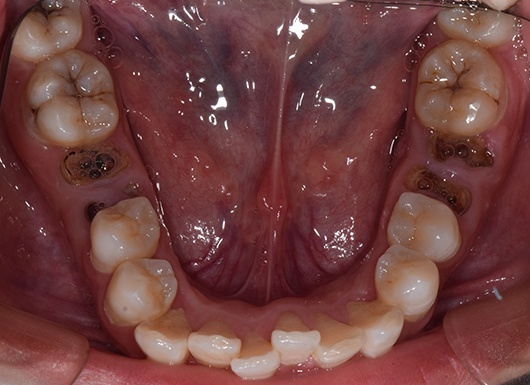

首先第一个是因为六龄齿已经蛀到只剩残根,拔除后我们打算把第二磨牙和智齿前移,关闭拔牙间隙,使智齿变废为宝。

第二个case是已经开始矫正了一年半,当初智齿还是阻生的,但角度很好,经过矫正,今天黏上颊面管,纳入矫治,已经变废为宝了,六龄齿的间隙快要被完全关闭了。这样做当然比拔除两个第一前磨牙排齐所费周章,但能多保留两个天然健康的牙齿,也是一辈子收益的。